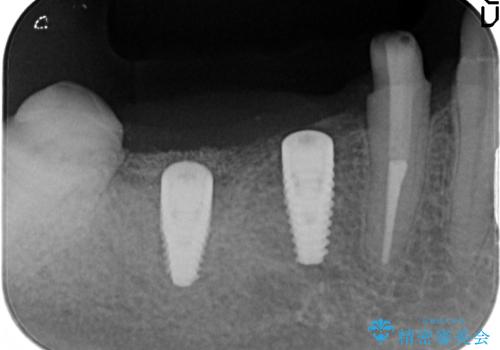

- 右下でものを咬むと痛むので診て欲しいといらっしゃった方の症例です。

右下6番目の歯を診査したところ歯根が破折していたため、保存不可能であることを説明し抜歯しました。

その後右下5、6番目にはインプラントを埋入し、右下3、4、5、6、7番の歯の補綴をオールセラミッククラウンによって行いました。

- オールセラミッククラウン…¥100,000×5、仮歯…¥10,000×5、インプラント(ストローマン)…¥200,000×2、カスタムアバット…¥100,000×2、骨増生…¥50,000費用は治療当時の料金となります

当院では主にストローマンという種類のインプラントを治療に用いています。

ストローマンは世界的にもNo1のシェアを誇り、骨との適合にも優れたインプラントです。

カスタムアバットメントは患者様それぞれの歯茎に合わせて製作されたオーダーメイドのアバットメントです。

既製のアバットメントに比べ適合がよく、高い清掃性を誇ります。